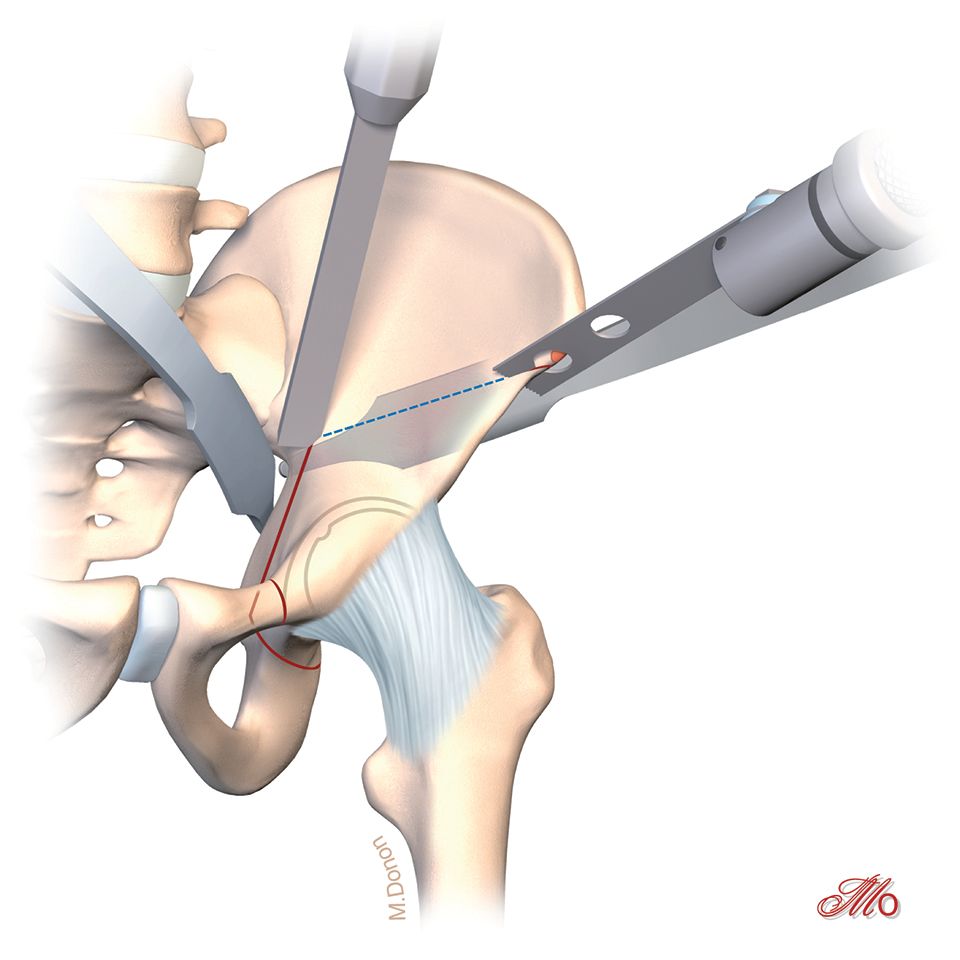

The retroacetabular osteotomy is performed at an angle of 110° relative to the supraacetabular osteotomy under fluoroscopic control (Fig. 14). Care must be taken to maintain a minimum bone stock of 1 cm prior to the sciatic notch to ensure the integrity of the posterior half of the posterior acetabular column. This ensures the continuity of the posterior column and provides the pelvic stability needed for postoperative mobilization and weight bearing.

After these osteotomies the acetabular fragment should be careful mobilized with a laminar spreader and 1 Steinmann-pin (Fig. 15). Often there are still same bone brides between the ischium and the retroacetabular osteotomies. These bridges should be brocken with a curved osteotome which is placed under fluoroscopic control and after spreading the osteotomy with a laminar spreader. After all osteotomies are finished, acetabular reorientation remains a difficult step and care should be taken to achieve proper acetabular reorientation. The goal of reorientation is an LCE of 30°, a positive acetabular index and an anteverted acetabulum The reoriented acetabulum is then temporarily secured by two Kirschner wires that bridge the supraacetabular osteotomy (Fig. 15).

The retro-acetbaular osteotomy should be centered in the posterior acetabular column and not be performed too close to the acetabulum. The bone stock directly behind the acetabulum is very thick and difficult to osteotomize. If the retro-acetabular osteotomy is not performed completely and too much force is applied via the laminar spreader during the reorientation of the acetabular fragment there is a risk of inducing an intraacetabular fracture through the acetabular fossa. The bone stock around the acetabular fossa is very thin and this area is at an increased risk of fracture if excessive force is applied during the reorientation procedure.

In case of difficulties to mobilize the acetabular fragment, the authors recommend the insertion of a lambot osteotome into the retroacetabular osteotomy to equally distribute the force across the entire posterior column of the acetabulum during reorientation. This maneuver gives the surgeon very good feed-back regarding the mobility of the fragment and if needed the incomplete osteotomies can be checked and performed again.